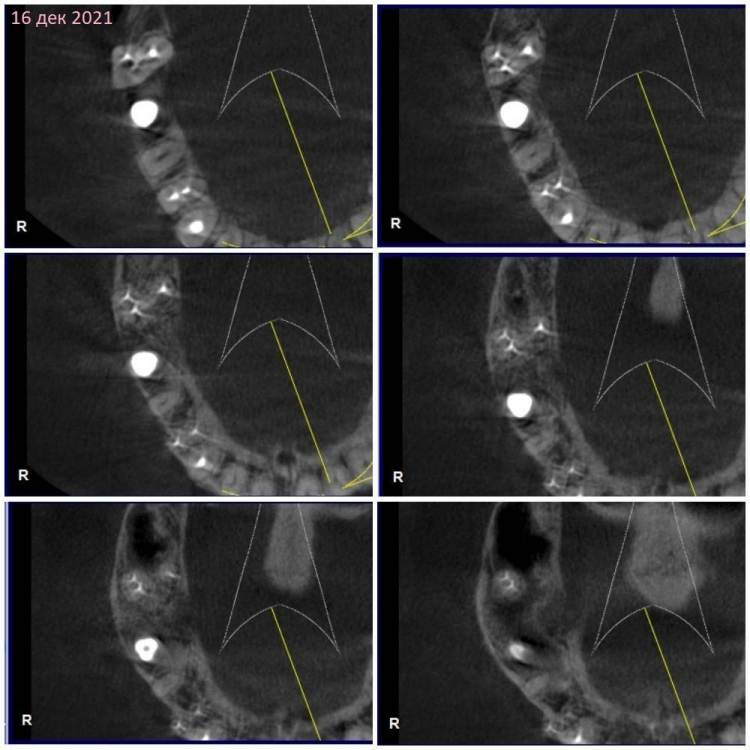

Сентябрь 2021 – удалили 16й с одномоментной имплантацией и подсыпкой кости, сразу поставили формирователь.

Недавно с ужасом обнаружила, что 17 сместился в сторону импланта 16, уткнувшись в формирователь(

3.  Почему так быстро сместился 17 в сторону 16? И помешает ли это при установке коронок на 16, 17?

КТ наскринила парочку. Если нужно будет более подробно – выложу еще.

302205257_3162021.thumb.jpg.18a720cc1985f835a447cc570076ff9a.jpg

409358705_1620212.thumb.jpg.217d1a7f90d9ddcd10fa9fa074c4e53f.jpg

1663100281_1620211.jpg.bf12cf24a1038fe62444cbec72388c0a.jpg

230110228_1620213.thumb.jpg.2a516e39278fed762fb4f254cd64fd77.jpg